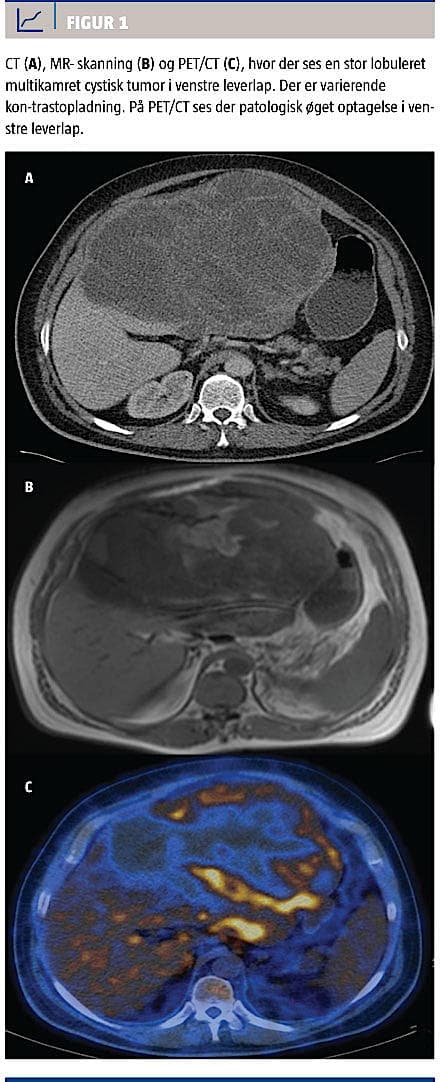

Med henblik på at karakterisere tumoren og visualisere eventuelle ekstrahepatiske fund blev der foretaget standard-CT af thorax og abdomen med i.v. nonionisk kontrast. CT’en viste en multikamret, cystisk, hypodens tumor med diskret opladning i kanten samt forstørrede lymfeknuder i retroperitoneum og porta hepatis. Der var ingen fjernmetastaser.

En flerfaset MR-skanning med 1,5 T-skanner viste en multikamret tumor, der var overvejende cystisk og med septae, men også enkelte solide komponenter. Blandet signal i cysterne tydede på hæmoragi i tumoren. På T1-vægtede billeder havde tumoren lavt signal og på T2-vægtede højt signal. Efter indgift af i.v. kontrast var der stedvist let opladning i kanten og centralt i den tidlige fase, men der var ikke sikker udvaskning i den sene fase.

Ved fluordeoxyglukose-PET-CT var der patologisk øget optagelse mellem de cystiske processer med standardized uptake value maks. 5,7 g/ml og let øget optagelse i enkelte portale lymfeknuder (Figur 1).